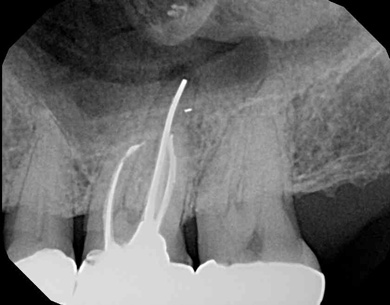

Fig 4.  Due to reported allergies to resin-based materials and eugenol, obturation was completed with a calcium hydroxide-based sealer (Figure 4 and Figure 5) with healing noted at a 1-year follow-up (Figure 6).

Figure 4

Fig 5.  Due to reported allergies to resin-based materials and eugenol, obturation was completed with a calcium hydroxide-based sealer (Figure 4 and Figure 5) with healing noted at a 1-year follow-up (Figure 6).

Figure 5

Due to reported sensitivities by patients to certain materials, the use of alternative materials does occasionally become necessary.  The endodontic literature demonstrates the safety and efficacy of calcium hydroxide-based sealers, and consequently these represent a suitable alternative (Figure 4 through Figure 6).